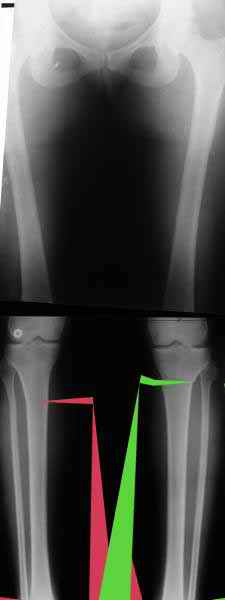

AC> Обратилась дама 25 лет. Вынуждена ходить в брюках из-за genu varum,

AC> что побудило обратиться за коррекцией.

Сейчас это модно (в смысле косметическая коррекция)... Хотя, судя по фото - в данном случае енто вполне оправдано...

Судя по снимку у девушки имеется внутренняя установка надколенников...

Как у нее с торсионным статусом? Бедро? Голень? КТ? Торсиометры? А то, куда будут

смотреть надколенники после вашей коррекции - тоже существенный

косметический момент. Или не так?

AC> Вот, с учетом и без учета, и на разных уровнях...

Из приведнной схемы не совсеим понял что означают разноцветные линии.

И зачем латерализация периферического фрагмента. Я всегда делаю медиализацию. См схему. И для данного случая медиализация подходит как нельзя лучше.

a> Из приведнной схемы не совсеим понял что означают разноцветные линии.

Черные - это нынешняя механическая ось. Красные - это планируемая правильная ось.

a> И зачем латерализация периферического фрагмента.

;-) Читайте Палея. Стр. 114-115.

a> Я всегда делаю медиализацию. См схему. И для данного случая

Медиализация - это чисто эстетический прием, как я понимаю. Поскольку если делать остеотомию ниже вершины деформации, для восстановления оси надо делать смещение по ширине, в данном случае как раз латерализацию.